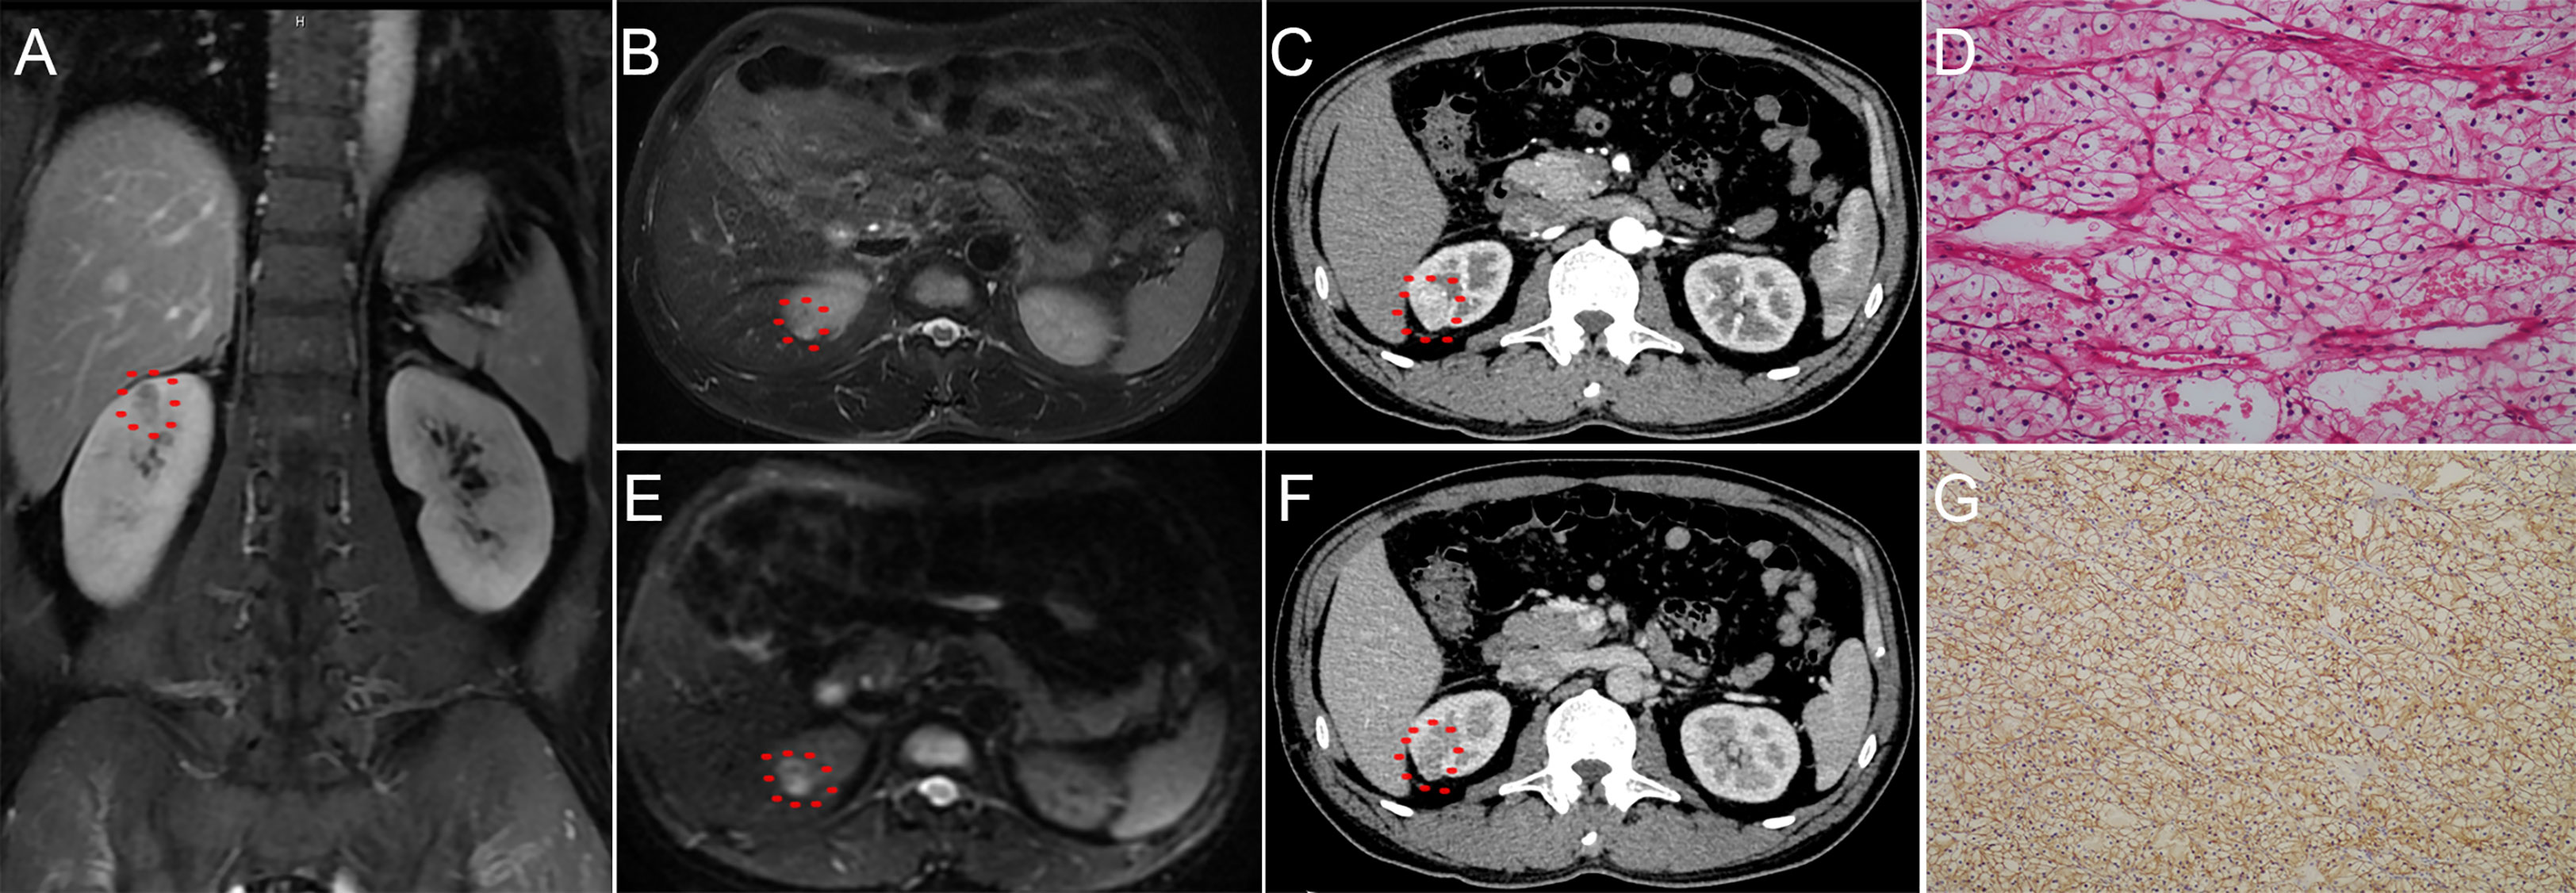

Predicting the risk of pT3a stage in cT1 clear cell renal cell

Evaluation of the Prognostic Significance of Perirenal Fat Invasion and